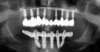

Le cliché panoramique permet d’apprécier l’ajustage des armatures usinées sur les piliers et la différence de contraste radiologique entre la zircone au maxillaire et le titane à la mandibule.